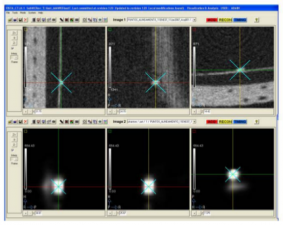

In this work we characterized a recently developed gamma imager for small animal SPECT applications. The Hamamatsu C9177 is a mini-gamma camera that integrates the detector and all the electronics, including the acquisition system, in a compact and portable housing. The detector is based on a high resolution parallel hole collimator, a CsI(NaI) crystal array and a PS-PMT (flat panel type). |

En este trabajo se ha implementado un prototipo de tomógrafo SPECT para animales de laboratorio, basado en el nuevo detector de radiación C9177 de la empresa Hamamatsu. El objetivo básicos de este desarrollo ha sido la evaluación de las características del elemento detector para su aplicación al SPECT de animales de laboratorio y por tanto la posibilidad de su utilización como elemento base en futuros diseños. Para caracterizar el detector, se han implementado los algoritmos estándar de corrección y se han evaluado los parámetros básicos de rendimiento antes y después de su aplicación.